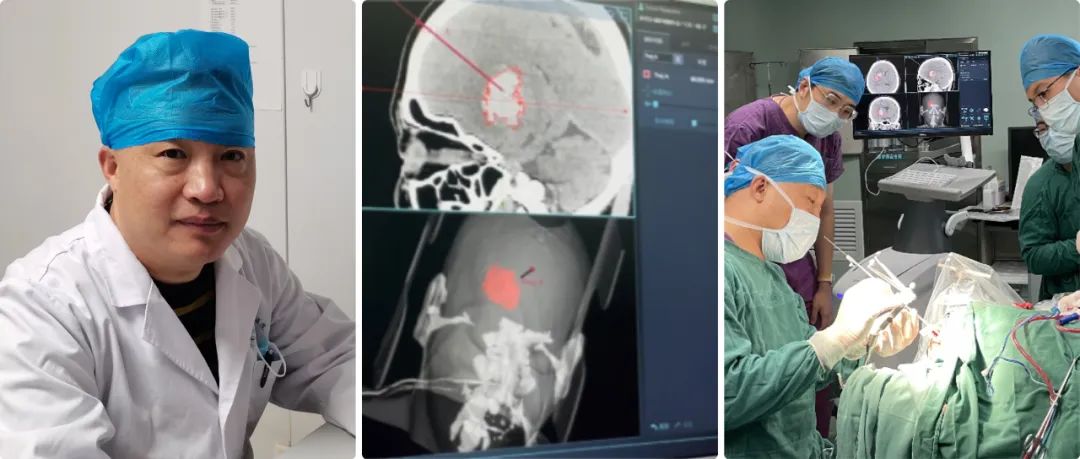

但是大部分病人虽然是脑出血,但是病人生命体征比较稳定,K8凯发国际尽可能用神经导航来实现微创血肿穿刺引流。

神经导航微创手术就避免了传统开颅手术的弊端,它可以实现精准穿刺血肿引流,病人一次性接受手术,恢复比较快,并对病人整体创伤很小。

高磊:准备做神经导航手术之前,K8凯发国际给患者进行颅脑CT薄层扫描,层厚大约在0.625毫米-1毫米,然后在神经导航系统进行重建,在重建虚拟像上选择合适的靶点。

靶点选择的三个原则:第一,从头皮到血肿的穿刺路径比较短;第二,避开大脑重要功能区;第三避开重要的神经血管。

K8凯发国际经过对病人注册,实现在电脑上与实际人头部位置融合,再根据电脑上确定的穿刺位置,选择实际病人颅上的穿刺位置,两者基本上重合,这样确保穿刺路径的精准性。

高磊:任何手术设备,尤其导航系统,漂移不可避免;Sinovation神经导系统的误差可以控制在0.5毫米左右。

K8凯发国际对脑组织等漂移怎么克服呢?第一精准定位,第二实时导航,就是穿刺点确定后,K8凯发国际顺利获得颅骨钻孔到达皮层,再进行一次注册和校正偏差,确保漂移减到最小的程度。